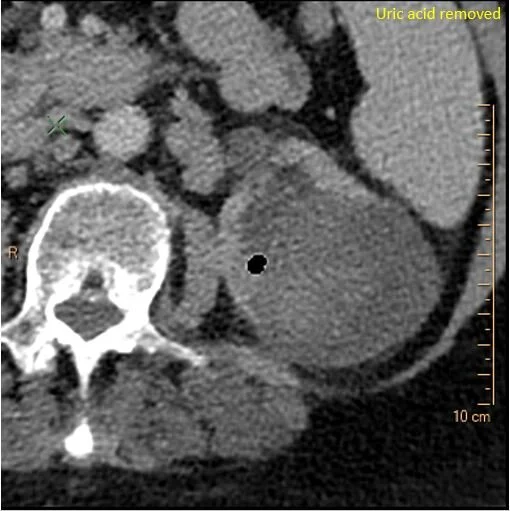

Spectral CT with uric acid removed shows the stone turns black, proving this is made of uric acid. This was confirmed after stone removal, on calculi analysis.

Uric acid removed: The stone is made of uric acid!